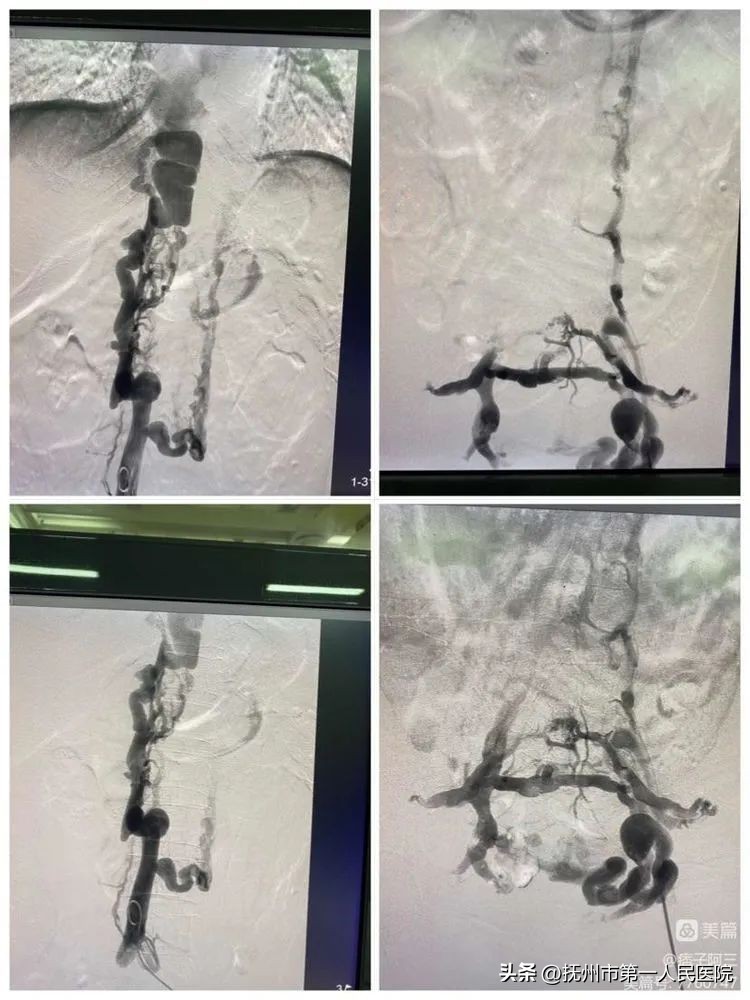

为了尽快给患者早期治疗指明方向、胡伟在导管室数字减影血管造影机的引导和监视下,为患者实施下腔静脉造影。通过血管造影,最后明确诊断为:复杂性布加氏综合症(下腔静脉阻塞型)。

给予完善相应检查、血液检查发现白细胞降低血小板板减低。

和患者及家属沟通后、在局麻下为陈女士进行了下腔静脉造影、下腔静脉开通、球囊扩张成形、支架植入术。手术过程中患者生命体征平稳,进展顺利。

术中再次造影、明确具体狭窄情况